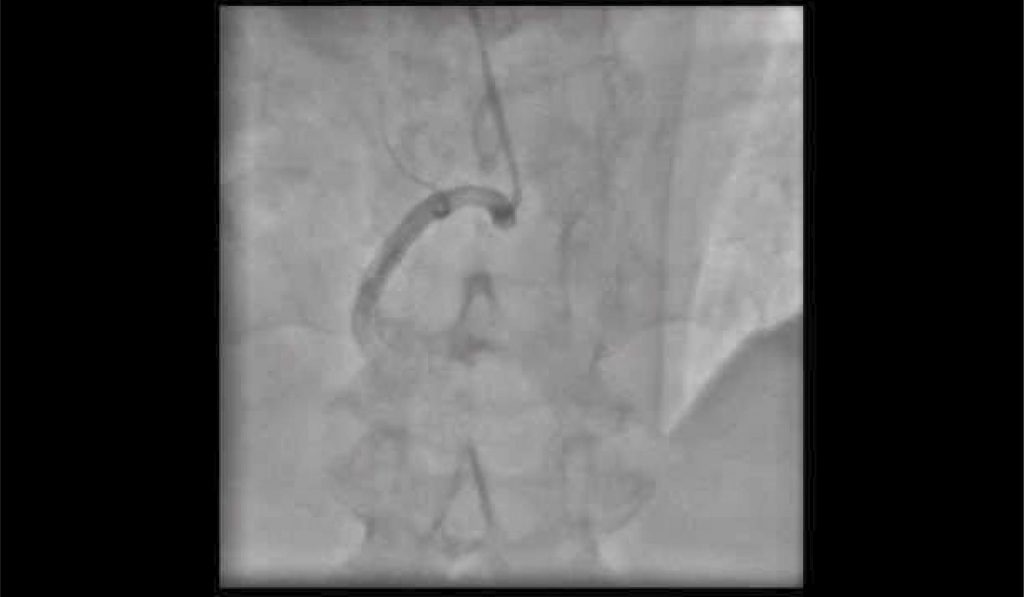

Vídeo 1

Colaterais Rentrop 3 bem desenvolvidas da artéria coronária direita para a descendente anterior.